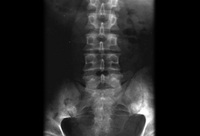

Spine radiograph: the "winking owl" sign (asymmetrical appearance caused by destruction of the pedicle)

Courtesy of Dr D. Park; used with permission

The "winking owl" sign (arrow): asymmetric appearance of spine on plain radiographs caused by destruction of the pedicle

Created by BMJ Publishing Group